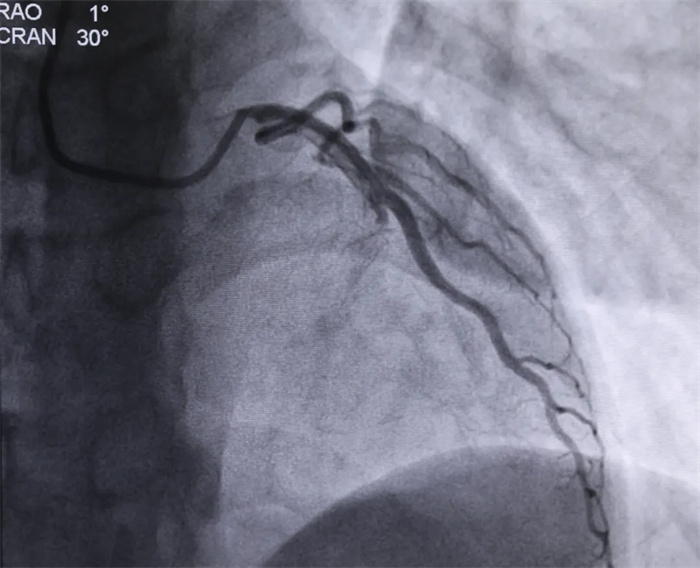

術(shù)前冠脈造影

心血管內(nèi)科主任朱永彪得到消息后,第一時間做好了手術(shù)準備工作。上午11點零6分,患者被推入導(dǎo)管室,急診PCI介入治療即刻開始:冠脈造影顯示,該患者左前降支近中斷完全閉塞并伴有血栓影,經(jīng)過術(shù)中短暫討論,行前降支介入治療。血栓抽吸后,于前降支中斷植入生物可降解支架。行血管內(nèi)超聲檢查后,可見支架貼壁良好,管腔基本恢復(fù)正常。最終造影顯示支架擴張滿意,無殘余狹窄,前向血流TIMI3級,患者胸痛癥狀得到明顯改善。目前,該患者生命體征正常,正在ICU接受進一步觀察治療。